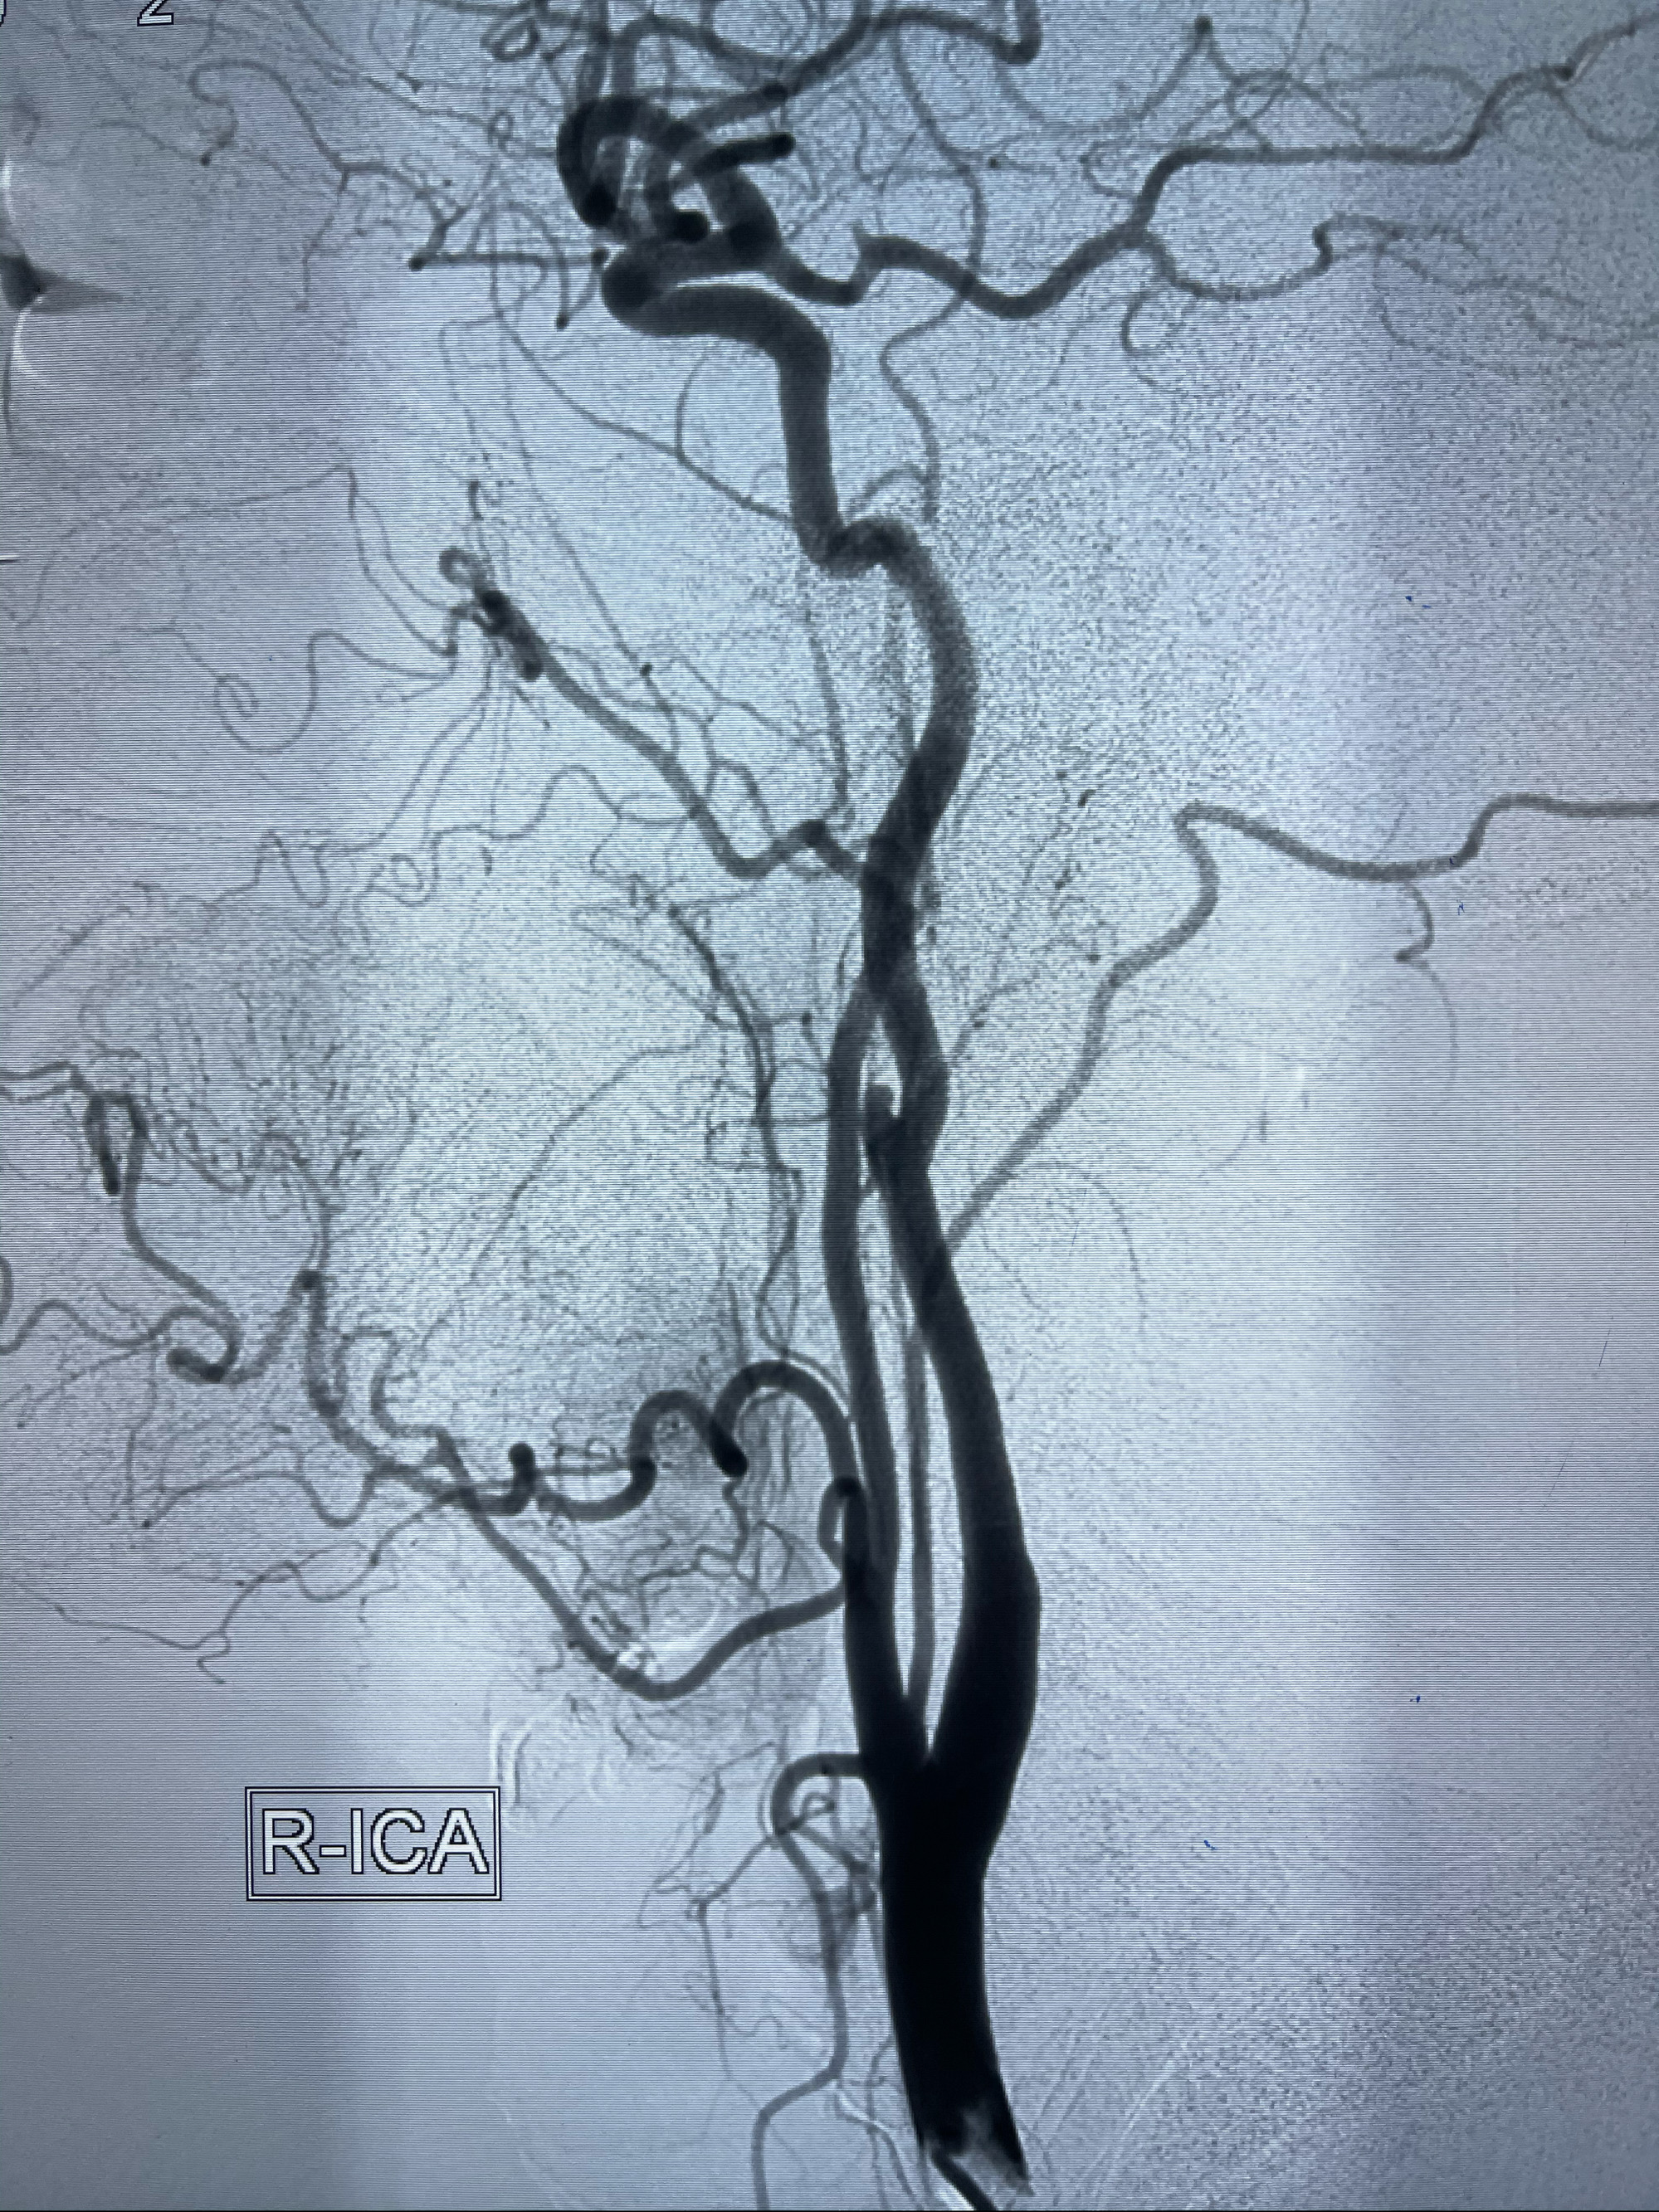

2021-03-08行全脑血管造影

1.右侧颈内动脉夹层动脉瘤Lvis支架辅助;

右侧颈内动脉夹层动脉瘤Lvis5.5-20mm支架辅助栓塞